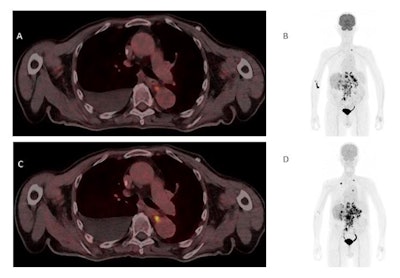

Both single and dual-tracer PET/CT were tolerated well by all patients, without any recorded adverse reactions or side effects, and all primary tumors could be clearly detected on both scans. However, in one patient, F-18 FDG revealed metastasis in only one mediastinal lymph node, whereas dual-tracer accumulation revealed two additional lymph nodes of the same drainage region.

One mediastinal lymph node of another patient showed discrete nonsuspicious F-18 FDG tracer accumulation, but suspiciously high dual-tracer accumulation. In addition, dual-tracer PET/CT displayed a higher number of liver metastases than F-18 FDG-PET/CT alone in a patient with a metastasis in the adrenal gland.

"The visual detection rate of suspicious lesions in single- and dual-tracer PET/CT showed equal results in four patients and superior lesion detection with dual-tracer PET/CT in two patients," the researchers wrote.